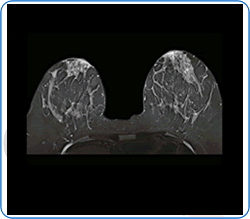

Breast MRI

Breast MRI is a diagnostic test that is used to view your breast tissues using magnetic fields and radiowaves (not X-rays).

The armpit tissues can also be seen on the scans.

Most patients do not require a breast MRI. It is used to provide further information in a variety of specialised situations, such as looking for possible breast implant leak, measuring lobular cancers, or for checking response to chemotherapy. Sometimes, a contrast dye (gadolinium) needs to be injected into a vein in the arm during the scan. Multiple images are obtained and these are normally reviewed by two independent radiologists before a final report is issued.